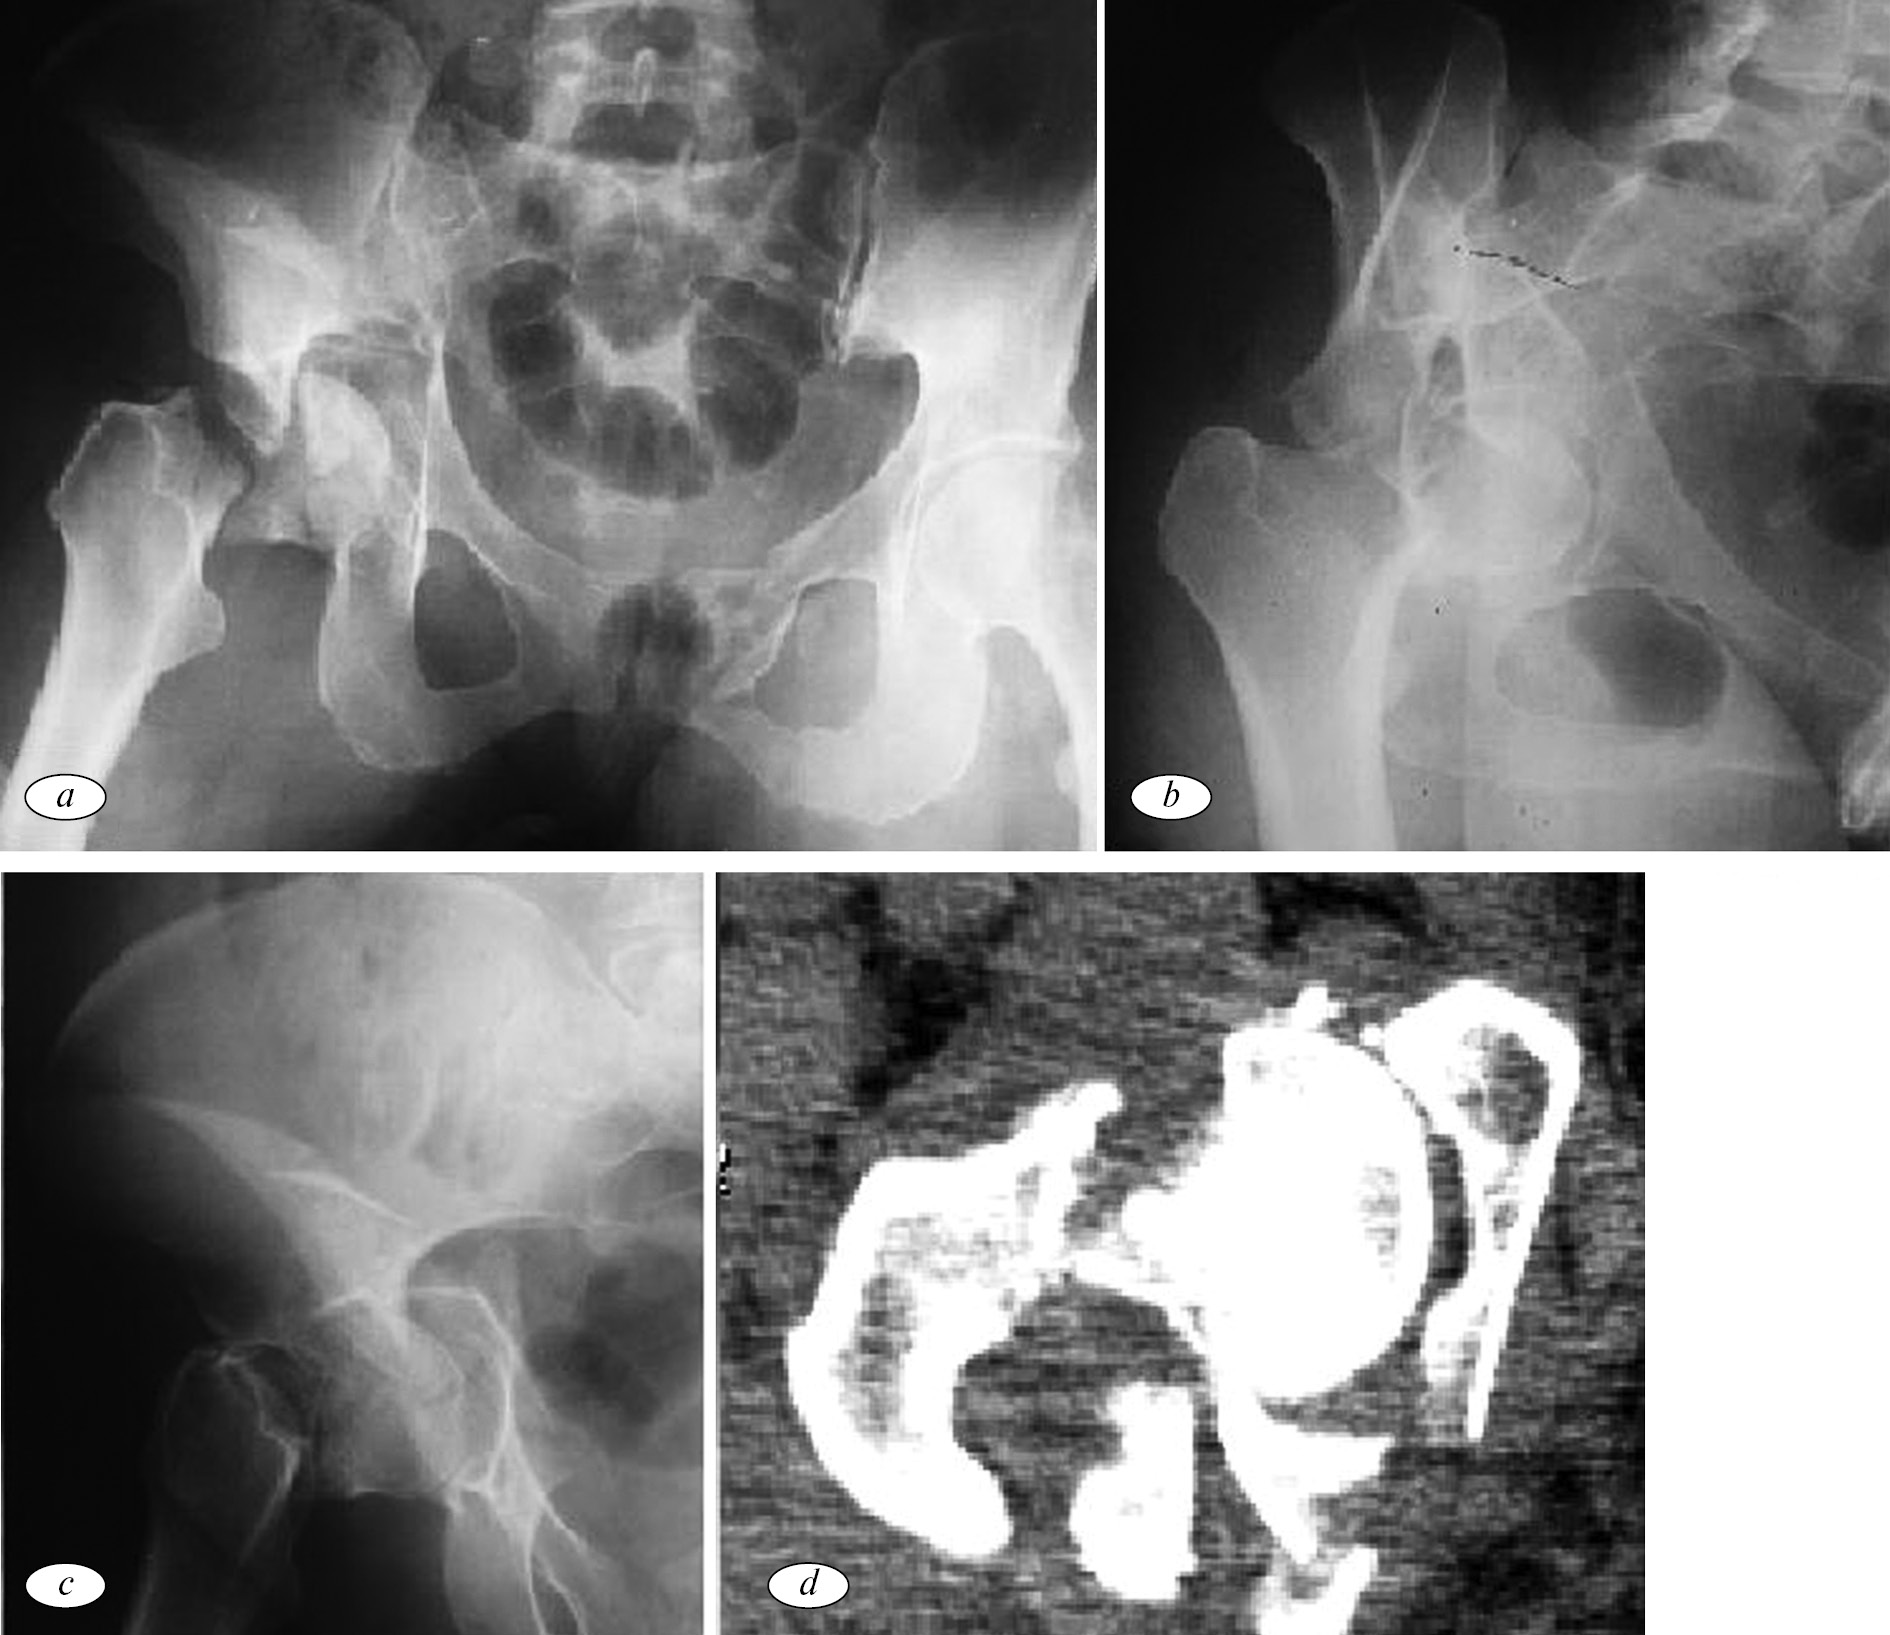

Через 6 мес. после травмы больничный лист был закрыт. На момент выхода на работу функциональный результат по Harris составил 92 балла. Пациентка ежегодно проходила контрольные осмотры травматолога с обязательной рентгенографией тазобедренного сустава. По истечении 5 лет было принято решение выполнить операцию — удаление канюлированных винтов из шейки бедра. Во время проведения операции удалось вынуть только один винт, а два других остались на месте по причине их интеграции в костную ткань (рис. 3).

Рис. 3. Рентгенограммы правого тазобедренного сустава пациентки Б. после неудачной попытки удаления канюлированных винтов, фиксирующих шейку бедра

Отдаленный результат прослежен до 10 лет. Со временем появились периодические невыраженные боли в области тазобедренного сустава и незначительная хромота, не ограничивающие привычную физическую нагрузку. По шкале Harris — 89 баллов, результат оценен как хороший.

В подтверждение адекватности выбранной хирургической тактики и применения имплантатов с покрытием на основе ПНКФК, несмотря на значительное разрушение костей тазобедренного сустава, был получен благоприятный клинический и рентгенологический результат. По прошествии максимального срока развития асептического некроза головки бедра при переломах вертлужной впадины и шейки бедренной кости (до 2 лет) [10, 12] была предпринята попытка удаления канюлированных винтов, фиксирующих шейку бедра. Два из трех винтов удалить не удалось по причине выраженной интеграции внешней поверхности имплантатов с костью.